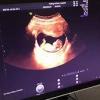

“唐筛”到底是什么?一定要做这项检查吗?下面就由佛山都市妇产医院妇产科主任医师为大家解答。...